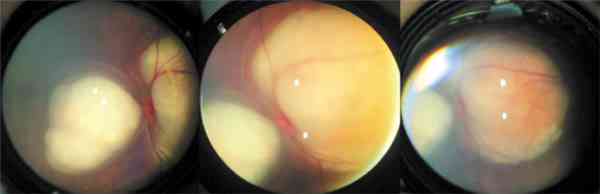

agradecimiento a todos por su colaboración.    Aplicación de termoterapia sobre un tumor de polo posterior. El

blanqueamiento indica el final de la terapéutica.